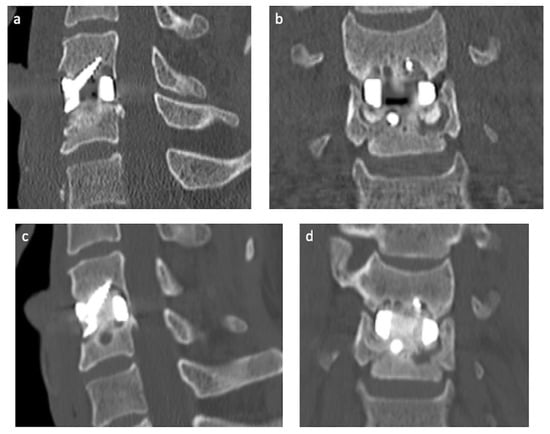

2.1. Case Presentation

2.2. Preoperative Planning

2.3. Operative Technique

3. Results